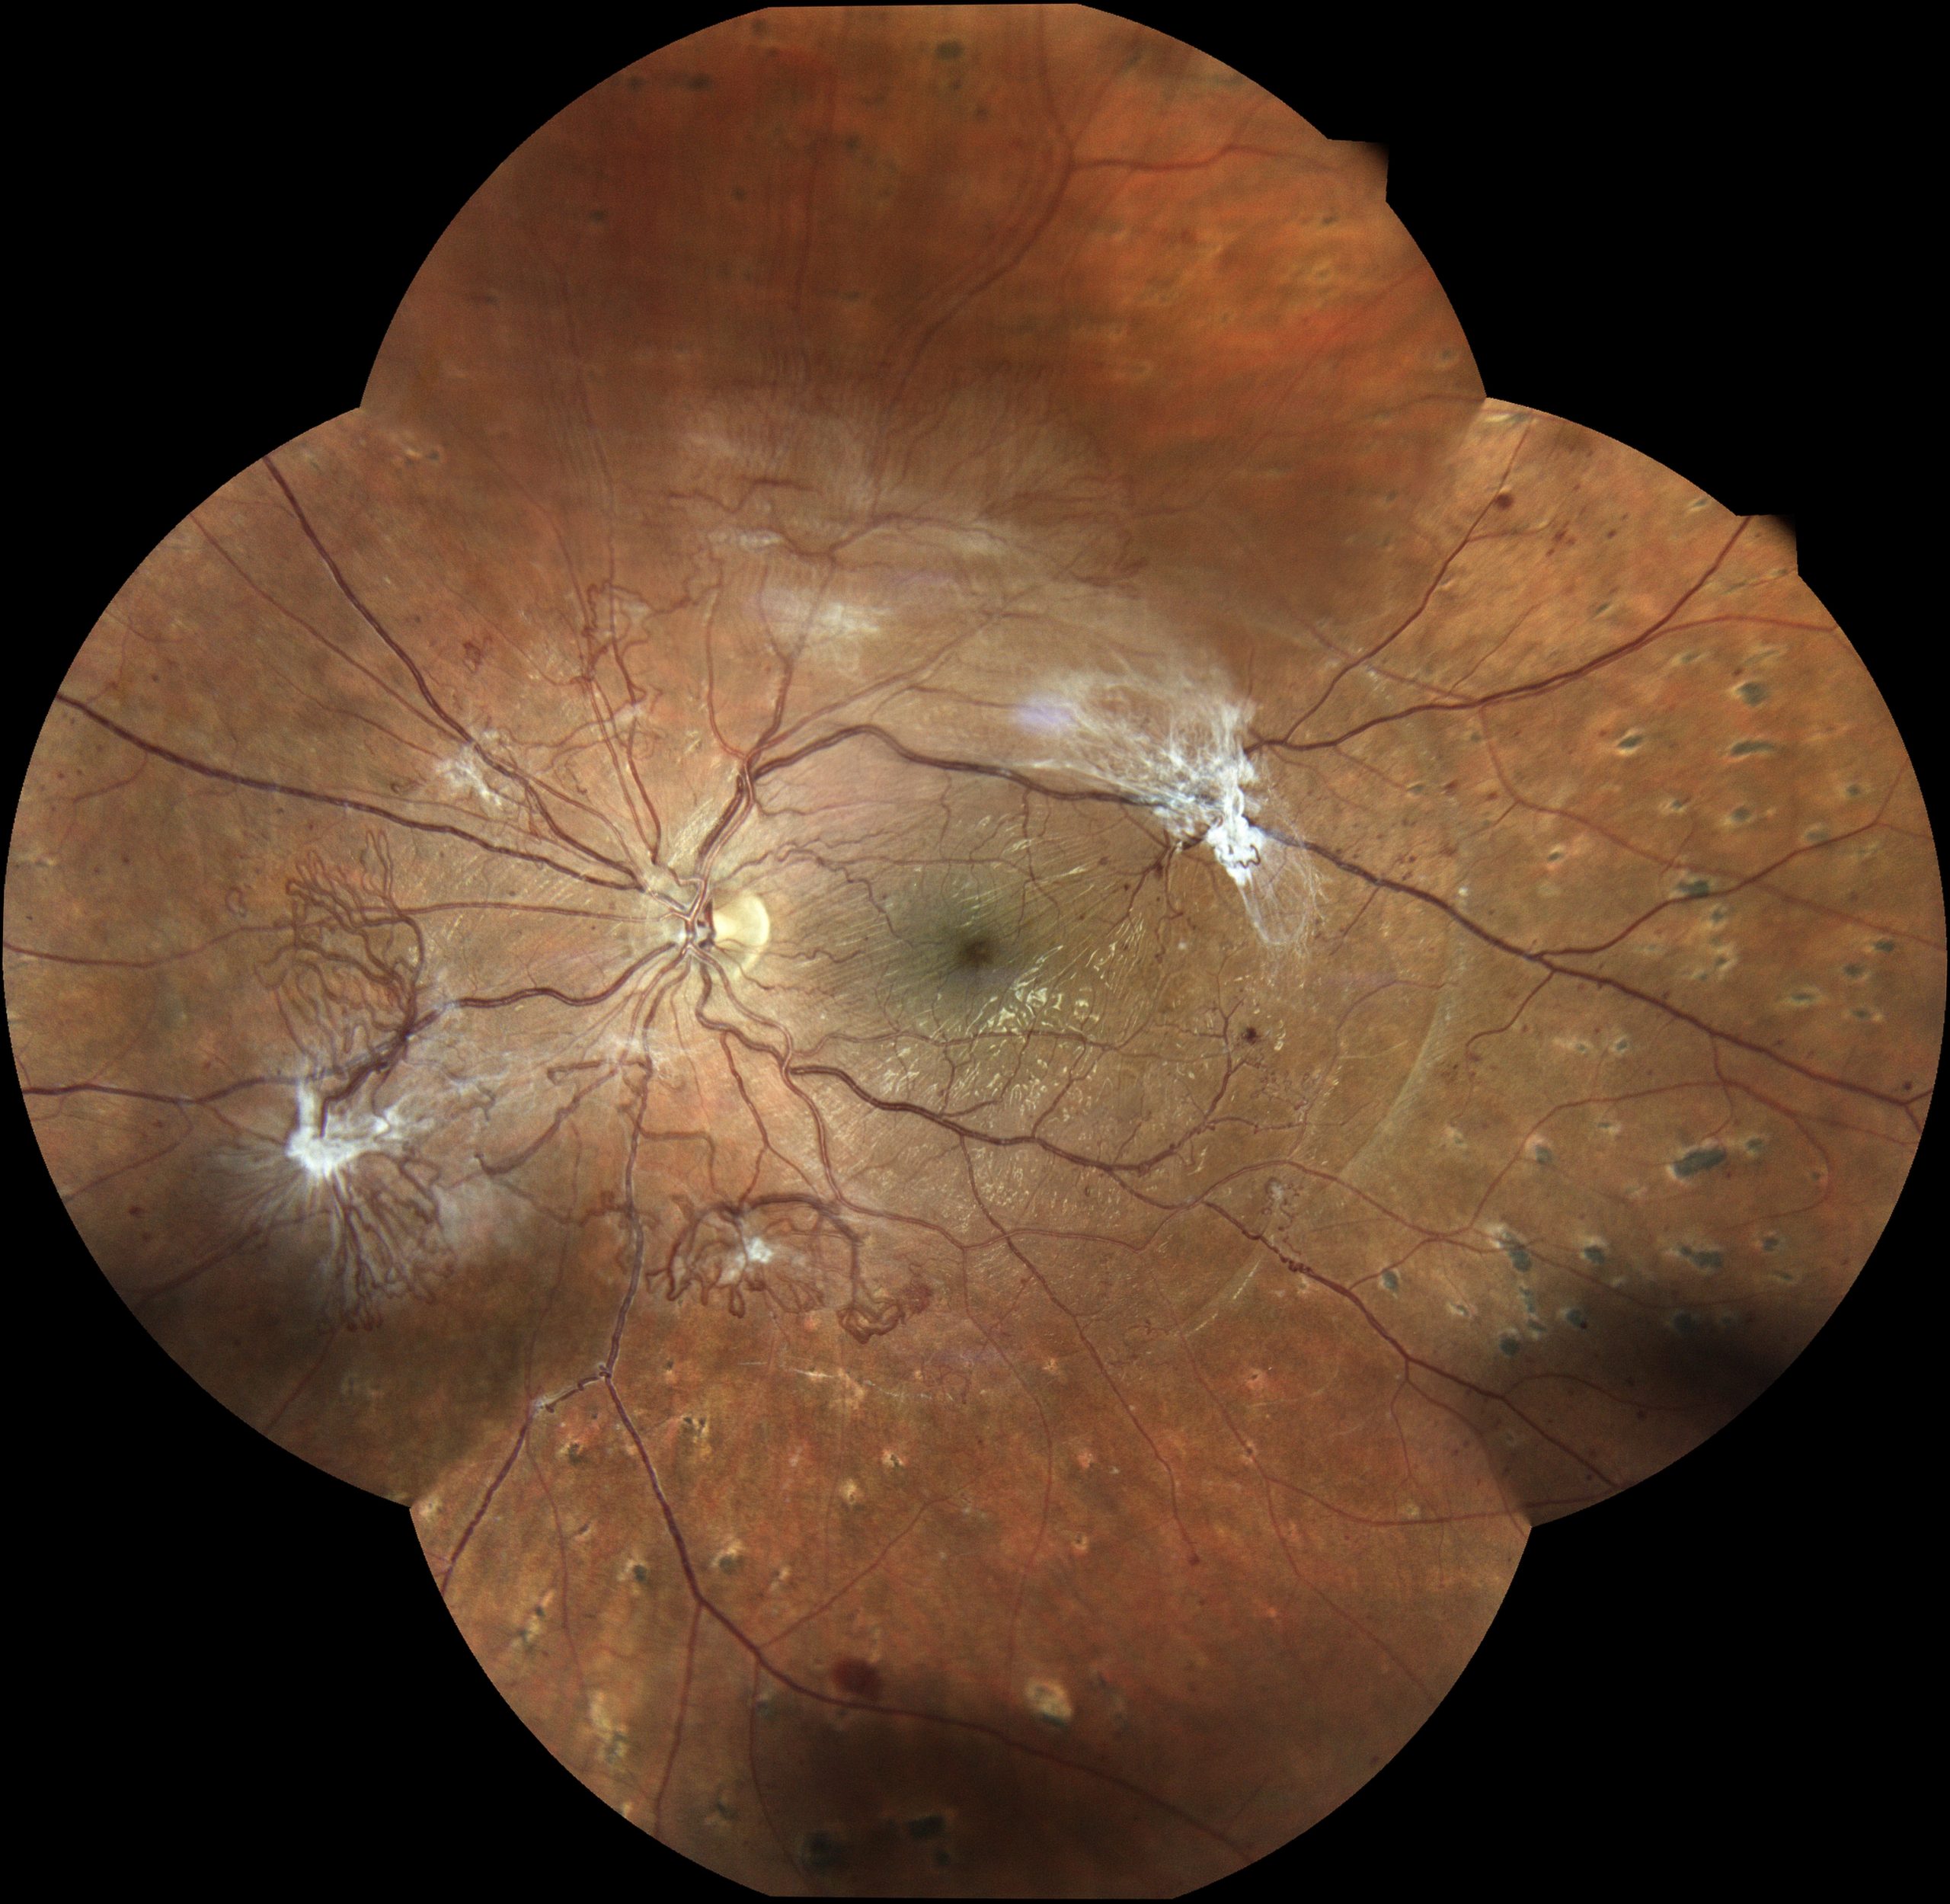

Jeder Augenarzt und jede Augenärztin kennt solche Beispiele aus der Praxis: Ein Patient kommt mit einem Bindehauttumor in die Praxis. Das kann ein harmloser Nävus sein – eine gutartige Fehlbildung wie es auch ein Muttermal ist (Abbildungen 1 und 2). Es kann aber auch ein bösartiger Tumor sein. Deshalb gilt es genau hinzuschauen und den Verlauf zu beobachten: Verändert er sich von einer Untersuchung zur nächsten? Dies lässt sich jedoch ohne eine Fotografie nicht dokumentieren. Ein anderes Beispiel ist das Netzhautscreening bei Menschen mit Diabetes: Sie sollen regelmäßig augenärztlich untersucht werden, um bei Schäden an der Netzhaut rechtzeitig reagieren zu können. Auch hier ist es unerlässlich, bei jeder Untersuchung Fotos der Netzhaut anzufertigen, um Veränderungen im Detail nachvollziehen zu können (Abbildungen 3 und 4).